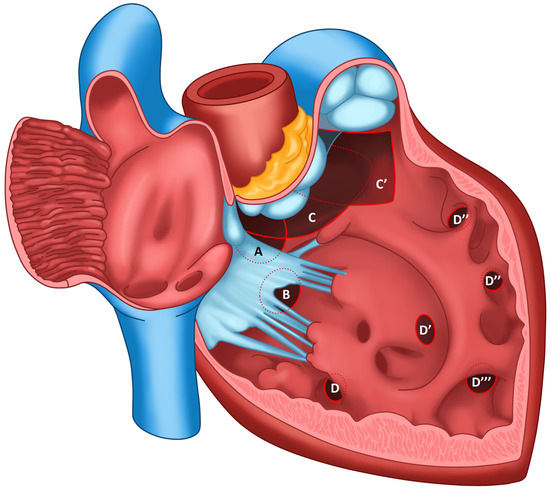

3. Nomenclature of Ventricular Septal Defects

1. Introduction